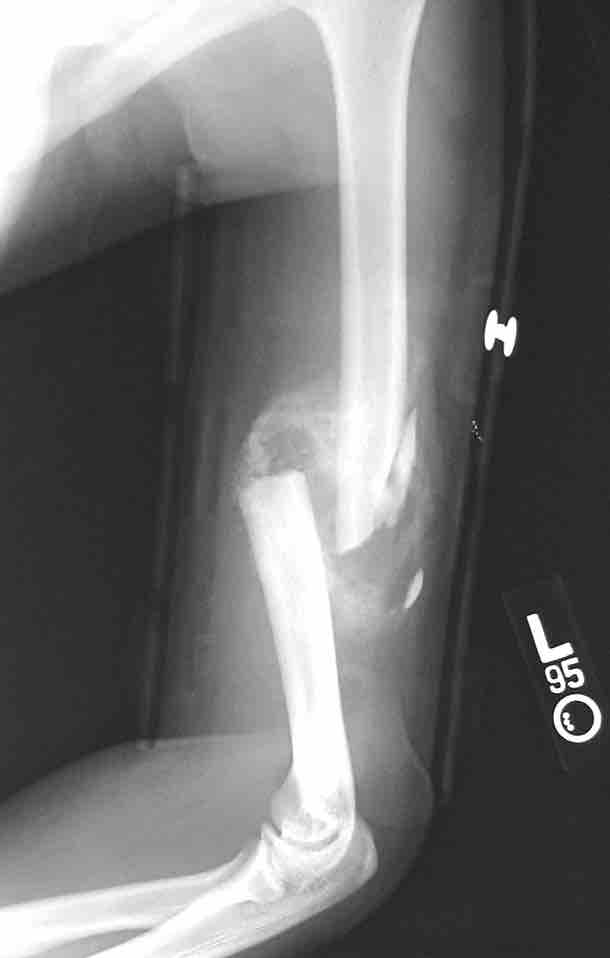

Bone repair

This figure depicts a communitive midshaft humeral fracture with callus formation.

This is an x-ray image of a broken arm. It shows a communitive midshaft humeral fracture with callus formation.